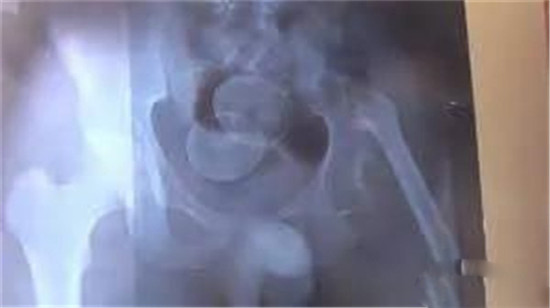

大肠里的擀面杖。男性

这是做饺子皮用的擀面杖。对,全部塞进去了。你知道怎么看男女吗?看骨盆的角度。

取出的方法如同上面。